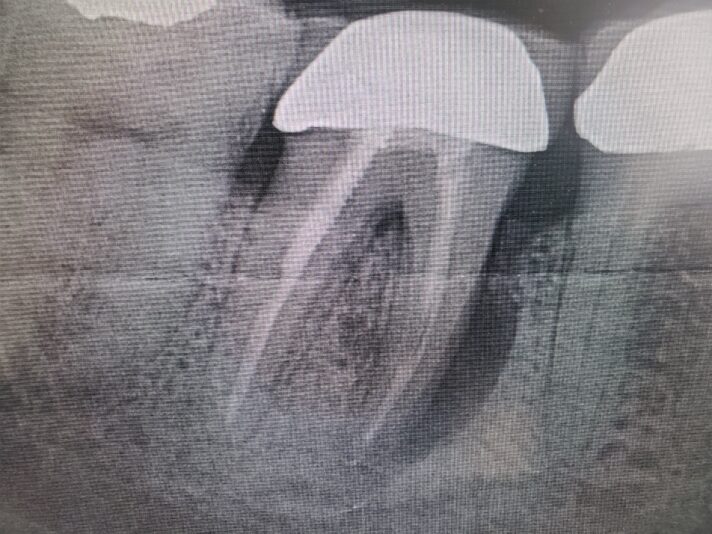

• I know this is an implant study club but I wanted to share a disappointment I had in my most recent bone graft. Patient came in for second opinion and after going over options and non restorable #31 I extracted and grafted the site. Post op PA showed that the M canal and defect was still present. This did have a buccal wall defect and I placed…

Read more